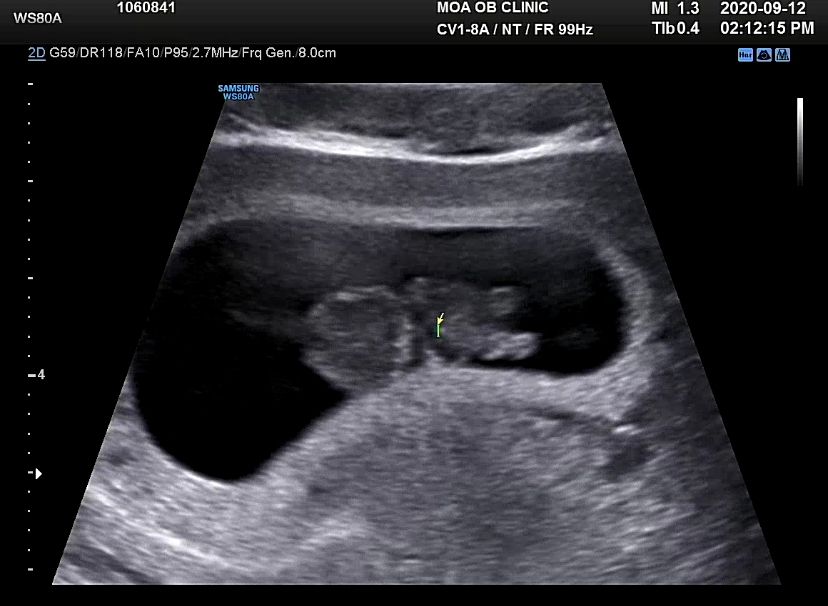

Мои неделькиДевушки,всем добрый вечер🌸У меня непонятные ощущения в матке..сейчас идёт 13-я неделя🤪Я когда хожу,не могу выпрямится,вот прям стягивает там все((вот будто пружины натянуты по всему брюху снизу вверх,и вот вот порвутся 😒когда чихаю,и смеюсь тоже неприятно,мимолетная боль такая проходит☹️У меня такое ощущение что там так органы сместились,что им как говорится «не дыхнуть,не пукнуть»😂может у кого так было??меня так это напрягает и переживаю..могу весь день проходить в загнутом виде😭наше первое фото